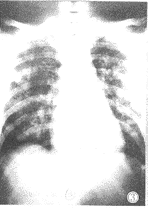

③弥漫斑片状和/或斑点状模糊影像,多沿支气管走行分布,常累及一侧或双侧肺野的大部,密度淡而不均,部分可融合成片状。本组10例,占12.8%(图3)。

图3 弥漫实变型:表现双肺野弥漫斑点状及片状模糊密度增高影,沿支气管走行分布,密度淡而不均,部分融合成片状。